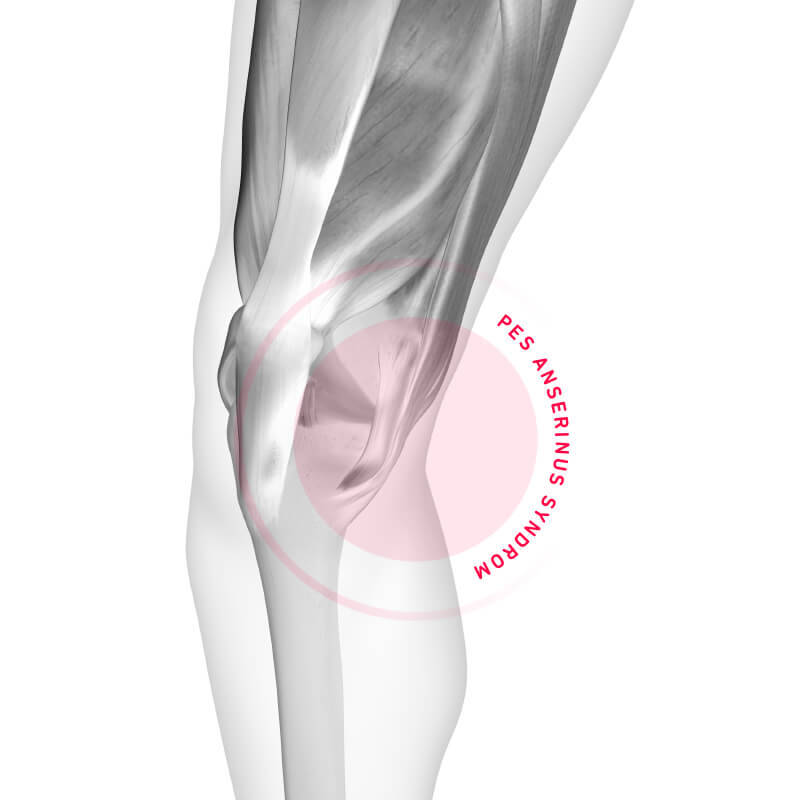

Pes Anserinus Syndrom

Wenn Läufer Schmerzen am inneren Schienbeinkopf haben, lautet die Diagnose oft Pes Anserinus Syndrom. Hier erfährst Du mehr über Ursachen, Symptome und Behandlung.